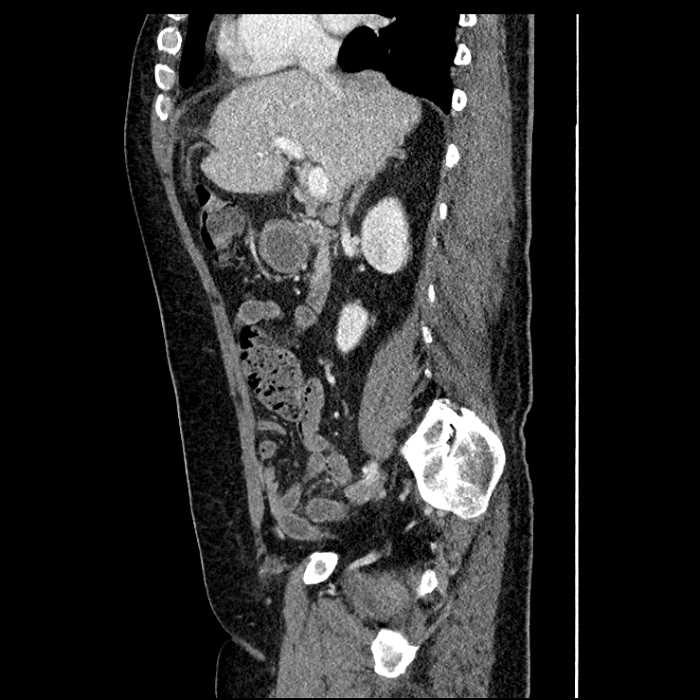

• Large fluid density structure in hepatic segments 7 and 8 measuring 10 x 7 x 7 cm with internal septation and circumferential ill-defined low density compatible with edema

• Peripherally enhancing subcapsular collections along the anterior margin of the left hepatic lobe measuring 3 x 1 cm and 2 x 1 cm

• Clearly marginated fluid density structure in segment 7 and several other scattered tiny hypodensities, which likely represent cysts

Acute sigmoid diverticulitis complicated by a small contained perforation and a large abscess in the right hepatic lobe. Additional small subcapsular abscesses along the anterior margin of the left hepatic lobe.

Additionally, loss of the normal fat plane between the peridiverticular collection and adjacent thickened loops of small bowel raises the potential for an enterocolonic fistula.

• The classic CT imaging appearance is a double target sign with internal low density surrounded by an internal enhancing rim (capsule) and a low density external rim (edema)

Hepatic abscess showing the double target sign with low density internally surrounded by a thin inner enhancing rim (red arrow) and ill-defined outer low density rim (yellow arrow). Blue arrow indicates an internal septation. Red arrows: additional smaller subcapsular abscesses. Red arrow: focal contained perforation associated with diverticulitis.